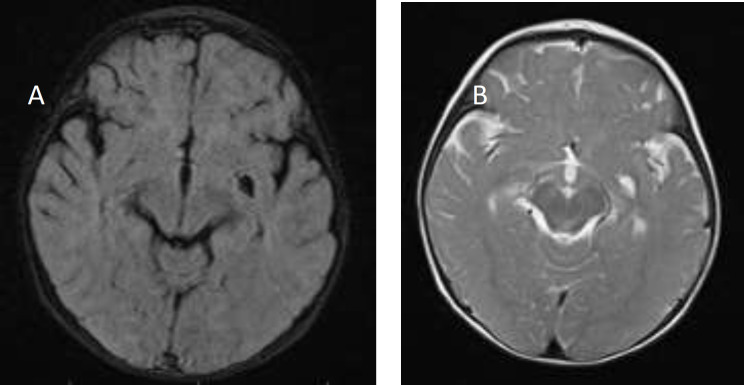

Ewing sarcoma (ES) is a highly malignant tumor originating from bones, exceptionally long bones. ES arising from the epidural extramedullary space, primarily the cervical region, is highly unlikely. There have been only six cases of cervical epidural extraskeletal Ewing sarcoma (EEES) in children reported in the literature, all of whom were older than seven years old. Four of seven cases, including the one mentioned in this study, were male (57%). Herein, we report a 1.5-year-old girl who presented with quadriparesis without cognitive impairment and had initially undergone a metabolic disorder evaluation. The spine MRI revealed a mass in the C2-T6 region, and she underwent a biopsy of the tumor via laminectomy. Microscopic examination confirms a diagnosis of ES based on immunohistochemistry. This is the first literature that presents an infant with EEES.